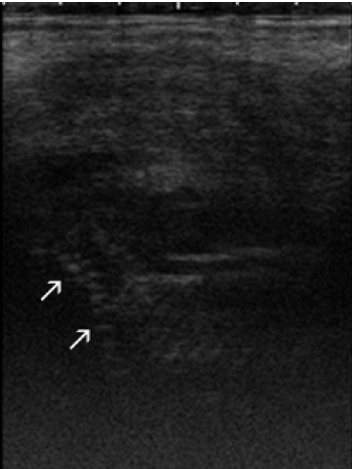

Hafez 2000), transrectal ultrasonografi (USG) (Yilmaz

et al. 2011) , x-ray (Dahiya dan

Bains 2014). Berikut adalah hasil pemeriksaan x-ray dan USG pada mumifikasi

fetus (Gambar 2a dan 2b).et al. 2011) , x-ray (Dahiya dan Bains 2014). Berikut adalah hasil pemeriksaan x-ray dan USG pada mumifikasifetus (Gambar 2a dan 2b).

Gambar 2b.

Ultrasonografi dari fragmen tulang

dari mumifikasi fetus sapi

FH usia 5 tahun (Yilmaz et al. 2011)